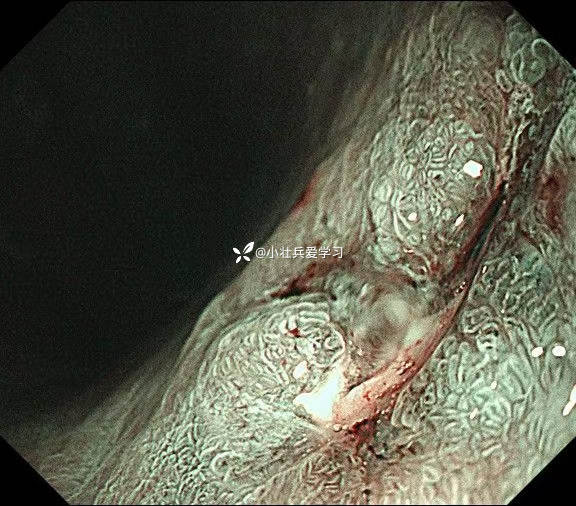

临床诊断:溃疡型胃角早癌

术前谈话诊断性ESD

术后病理示粘膜内癌(M3期),切缘阴性,达到治愈性切除标准,术后不用再追加外科手术、放化疗,对病人来说是不幸中的万幸。